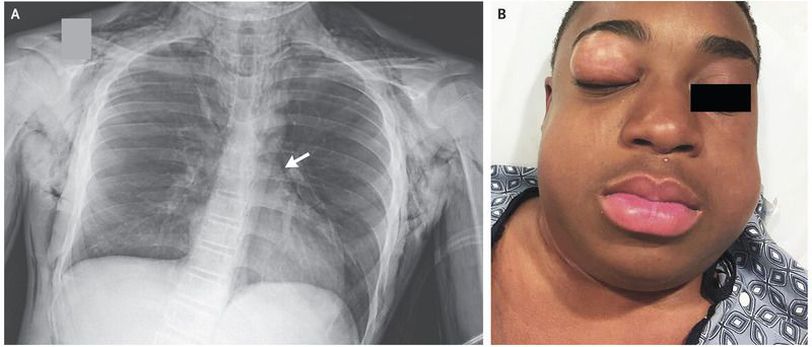

A 14-year-old boy with a history of asthma presented to the emergency department with a 1-day history of wheezing and coughing. His initial oxygen saturation was 83% while he was breathing ambient air, and the physical examination was notable for diffuse wheezing and the use of accessory muscles of ventilation. He received albuterol, ipratropium, intravenous magnesium, and intravenous glucocorticoids and was admitted to the hospital for a severe asthma exacerbation. Two days later, he had worsening respiratory distress and wheezing and was transferred to the pediatric intensive care unit for continuous albuterol treatment. Swelling and crepitus of the neck also developed. Among the findings on his chest radiograph was a pneumomediastinum (Panel A, arrow) with diffuse subcutaneous emphysema. Four days later, as his respiratory status improved, sudden swelling and palpable crepitus developed in both cheeks and the right eyelid (Panel B). He had no associated eye pain or diplopia, and extraocular movements were intact. Palpebral emphysema can occur as a complication of pneumomediastinum and typically resolves without intervention. On hospital day 7, the patient’s asthma exacerbation resolved and he was discharged home with intermittent albuterol treatment and a tapering course of prednisone. The eyelid swelling resolved slowly over 2 weeks.